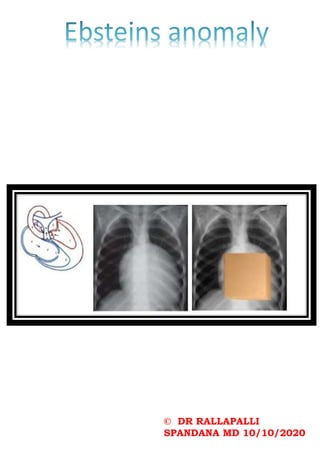

BULLET SHAPED METACARPALS

BEAKING OF VERTEBRA – bullet shaped

vertebra woth posterior scalloping